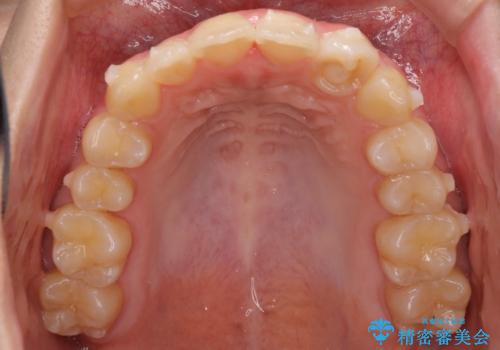

前歯のガタガタを目立たない装置でなおしたい インビザラインによる目立たない矯正

- 目立たない装置でガタガタをきれいにしたいとのご希望で来院されました。

インビザラインで矯正することとなりました。

左上の前から2番目の歯が通常とは異なる形態をしており、左右対称にすることはできませんでしたが、インビザラインで周りに気づかれることなく矯正治療をおえることができ、満足していただけました。